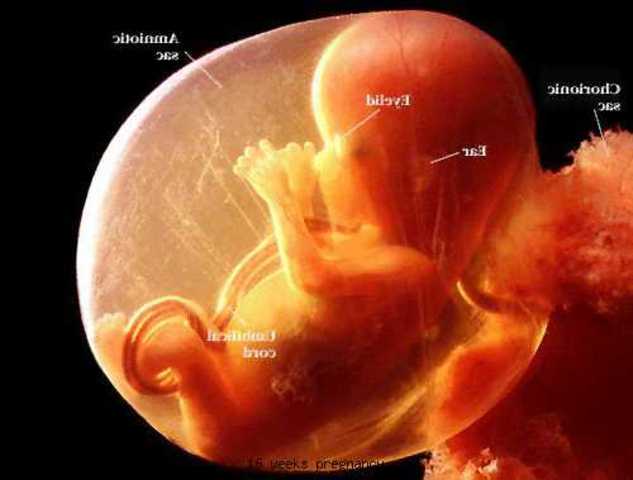

• Week 7

Week 7

Your baby is now about the size of a blueberry. Most of that growth is concentrated in the head as new brain cells are generated at the rate of 100 per minute. Your baby's mouth and tongue are forming as arm and leg buds sprout, and those little kidneys are getting ready to do their job (pee production and excretion). http://www.whattoexpect.com/pregnancy/week-by-week/week-7.aspx